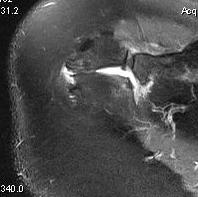

X-ray

Best seen on axillary lateral

Axillary lateral showing meso-acromion Scapula lateral xray showing os acromiale